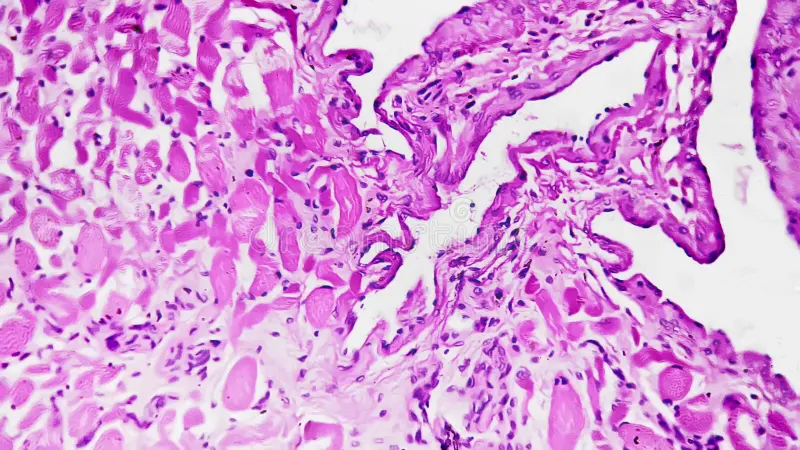

O que é Microscopia Vaginal?

É um exame realizado durante a consulta, em que analisamos uma amostra da secreção vaginal diretamente ao microscópio. Diferente da cultura tradicional — que pode levar dias para ficar pronta — a microscopia permite que o resultado seja avaliado na hora, identificando a composição da microbiota e sinais como presença de fungos, bactérias e desequilíbrios, para conectar a análise ao seu histórico, às suas queixas e aos próximos passos do tratamento.

Mais do que “confirmar uma suspeita”, o exame ajuda a diferenciar causas comuns de vulvovaginites e direcionar o tratamento com mais precisão, reduzindo erros e recorrências.

Microscopia e interpretação clínica

A análise do conteúdo vaginal ajuda a identificar padrões e sinais compatíveis com diferentes causas, apoiando uma conduta mais precisa.